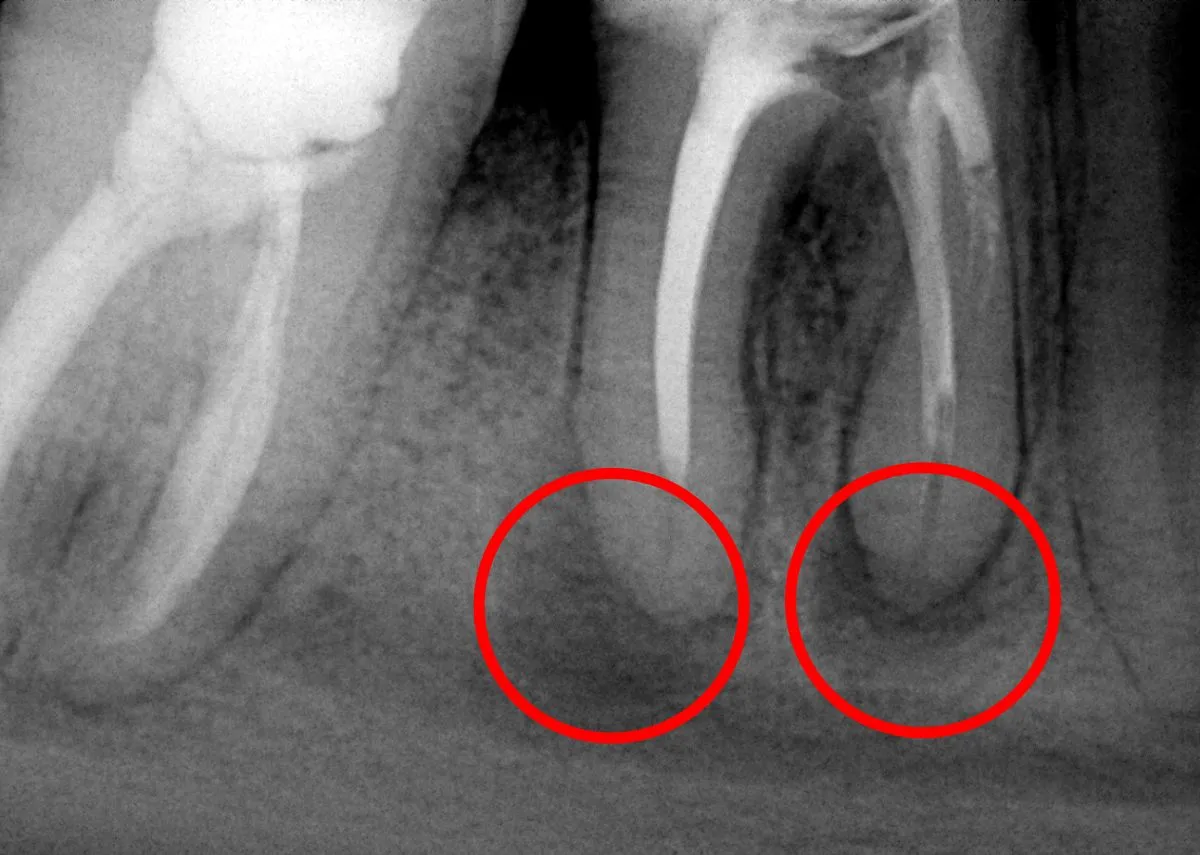

Samo badanie kliniczne w gabinecie stomatologicznym, choć jest pierwszym i niezbędnym krokiem, nie pozwala na pełną diagnostykę torbieli. Dlaczego? Ponieważ większość torbieli rozwija się w kości, pod powierzchnią dziąsła, co sprawia, że ich prawdziwy rozmiar, kształt i dokładne położenie są niewidoczne gołym okiem. Kluczową rolę odgrywa tu diagnostyka obrazowa. Tradycyjne zdjęcia RTG, takie jak zdjęcia punktowe (okołowierzchołkowe) czy pantomograficzne (panoramiczne), pozwalają na ogólną ocenę obecności i wielkości zmiany. Jednakże, aby uzyskać trójwymiarowy obraz i precyzyjnie ocenić torbiel w jej relacji do sąsiednich struktur, takich jak korzenie zębów, nerwy czy zatoki szczękowe, niezbędna jest tomografia komputerowa wiązki stożkowej (CBCT). To badanie dostarcza niezwykle szczegółowych informacji, które są nieocenione przy planowaniu leczenia chirurgicznego.

- Skierowanie na badania obrazowe: Po wstępnym badaniu, jeśli podejrzewam torbiel, zawsze kieruję pacjenta na odpowiednie badania obrazowe. Najczęściej jest to zdjęcie RTG punktowe lub pantomograficzne, a w bardziej skomplikowanych przypadkach tomografia CBCT.